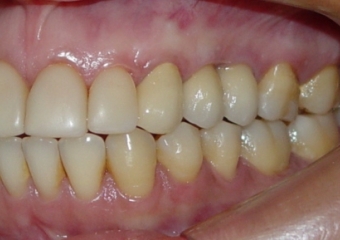

Imagem e sorriso final do caso terminado em junho de 2011